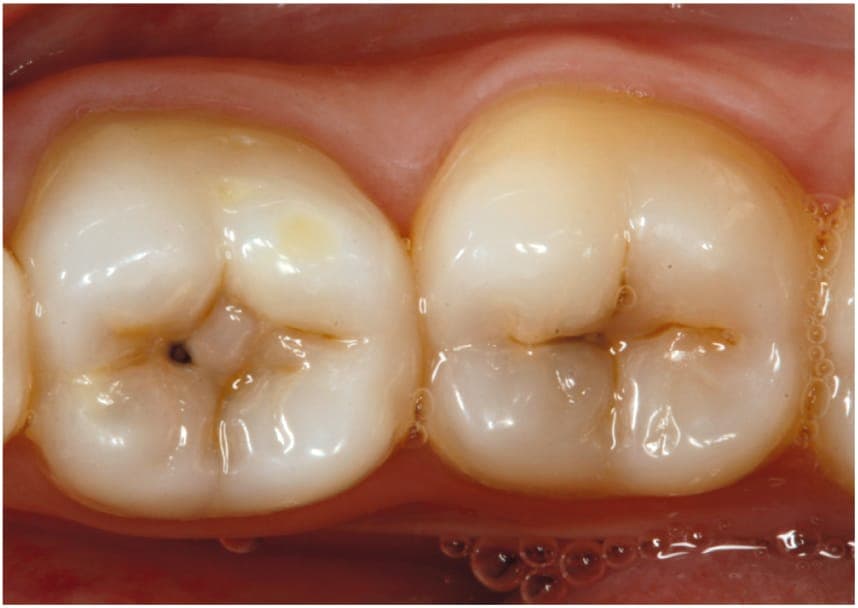

Adiar a ida ao dentista diante de um dente cariado ainda é uma prática comum entre muitos brasileiros. O que inicialmente pode parecer um problema simples, no entanto, pode evoluir para complicações graves na saúde bucal e até no organismo como um todo, alerta o cirurgião-dentista Paulo Grandal.

De acordo com o especialista, a cárie sempre começa de forma discreta, mas tende a evoluir com o passar do tempo quando não é tratada.

“O risco maior é a perda do dente. A cárie começa pequena e, conforme você não resolve o problema, ela vai aumentando”, explica.

Com o avanço da lesão, as consequências vão além do desconforto inicial. “O paciente pode ter dor, inflamação e, se essa cárie atingir partes mais profundas do dente, como o nervo, isso acaba causando dor intensa”, afirma Grandal. Ele compara o processo à ferrugem: “É como uma ferrugem na base de uma geladeira. Se não for removida logo, ela vai crescer cada vez mais”.